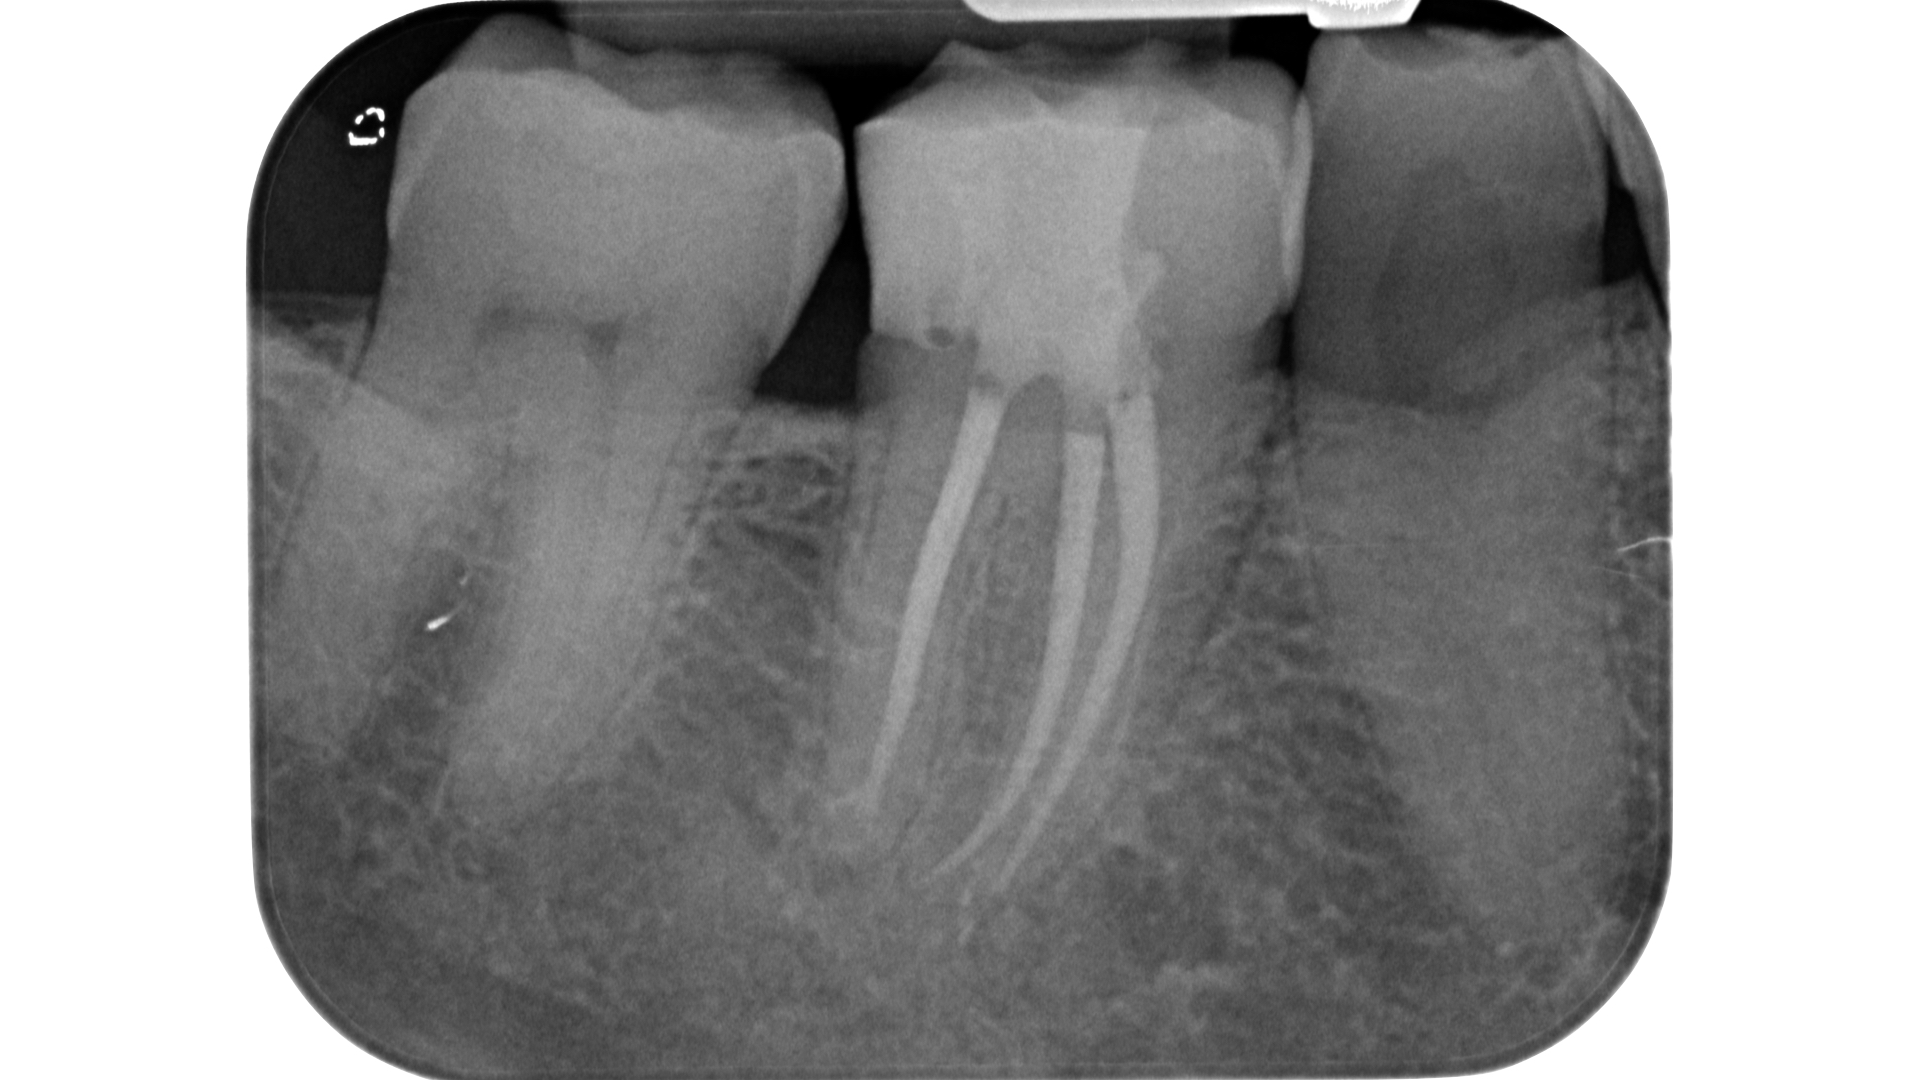

Lo step successivo, ossia l’esplorazione manuale e meccanica del sistema canalare, potrebbe nei casi più complessi essere impedito a causa dell’ostruzione dell’orifizio. Una calcificazione che si estende più in profondità rispetto al pavimento della camera pulpare può infatti rendere impossibile il sondaggio anche con lo strumento più piccolo a disposizione.

L’ostruzione, se estremamente limitata, può essere bypassata con un file montato su manico (micro-opener 10.04 15.04, Dentsply): questo strumento permette ottima visibilità e sensibilità rispetto ad un classico file manuale (Figure 21-26).

Una volta localizzata la traccia del canale è necessario cercare di sondarlo anche per pochi millimetri con un micro opener o un K file di piccole dimensioni 06 o 08.

In questa fase di esplorazione va riposta molta attenzione nell’evitare di ostruirsi di nuovo la strada in direzione apicale: questo è possibile grazie a ripetuti lavaggi e alternanza di tentativi di sondaggio manuale senza forzare e affrettare la discesa fino a lunghezza di lavoro. A differenza degli inserti ultrasonici che tendono a creare un invito spesso appuntito in direzione apicale e ad annullare almeno parzialmente le tracce cromatiche, l’utilizzo di strumenti rotanti strategici come Endotracer preserva questi fondamentali punti di riferimento e anzi facilita l’accumulo di detriti dentinali proprio dove c’è una naturale depressione, vale a dire il lume canalare.